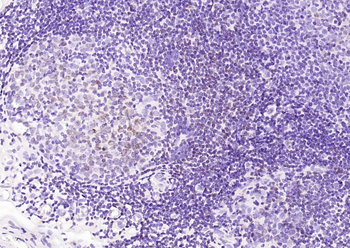

Recombinant HLA-DR (MHC II) Antibody

| Description | Recombinant HLA-DR (MHC II) Antibody |

| Tested applications | IHC |

| Reactivity | Human |

| Application notes | Positive Control: Human tonsil or lymph node |